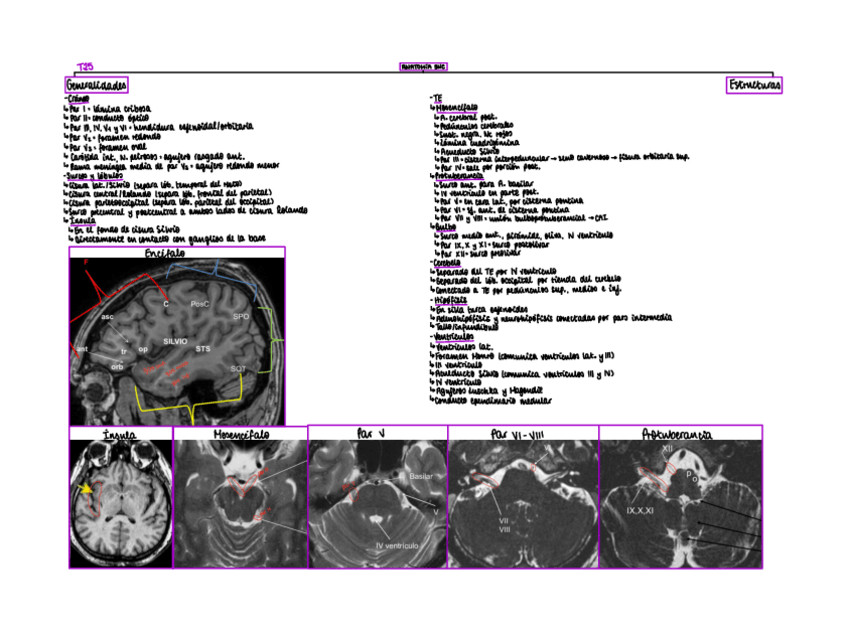

Tema-25-Anatomia-SNC.pdf

27.SemiologiabasicadelSNC.pdf